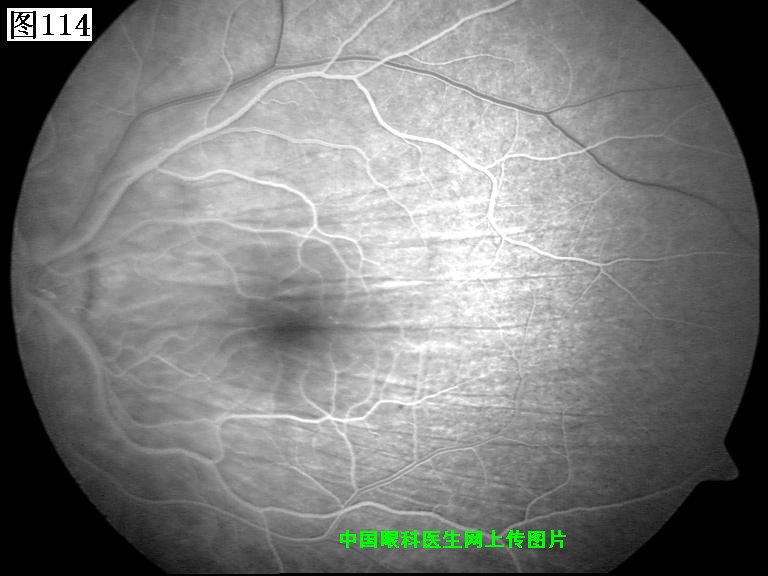

113 114 115 116